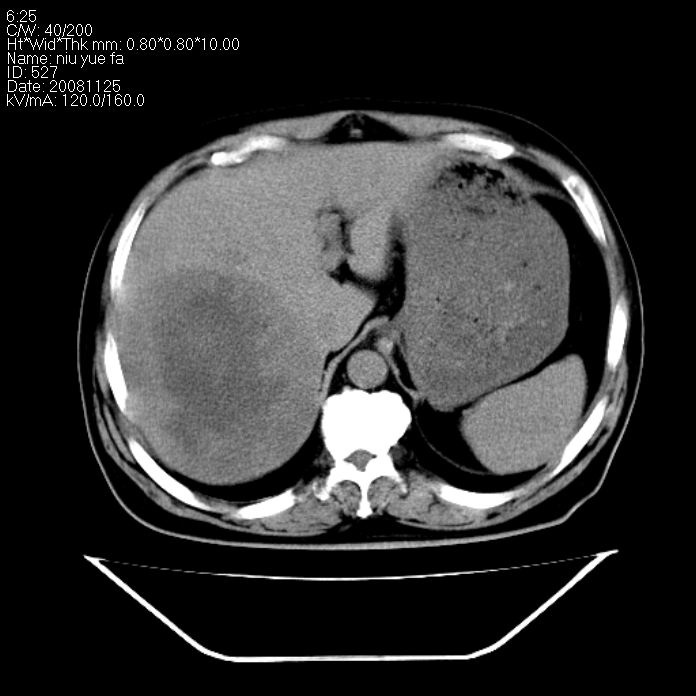

巨块型肝癌,坏死,出血;胆囊结石

1)考虑肝右叶巨块型肝癌并坏死、出血;建议行ct增强扫描检查进一步明确诊断。2)胆囊结石,胆囊炎。

考虑肝右叶巨块型肝癌并坏死、出血;建议行ct增强扫描。胆囊结石。

肝右叶巨块型肝癌并坏死、出血;胆囊结石,胆囊炎。